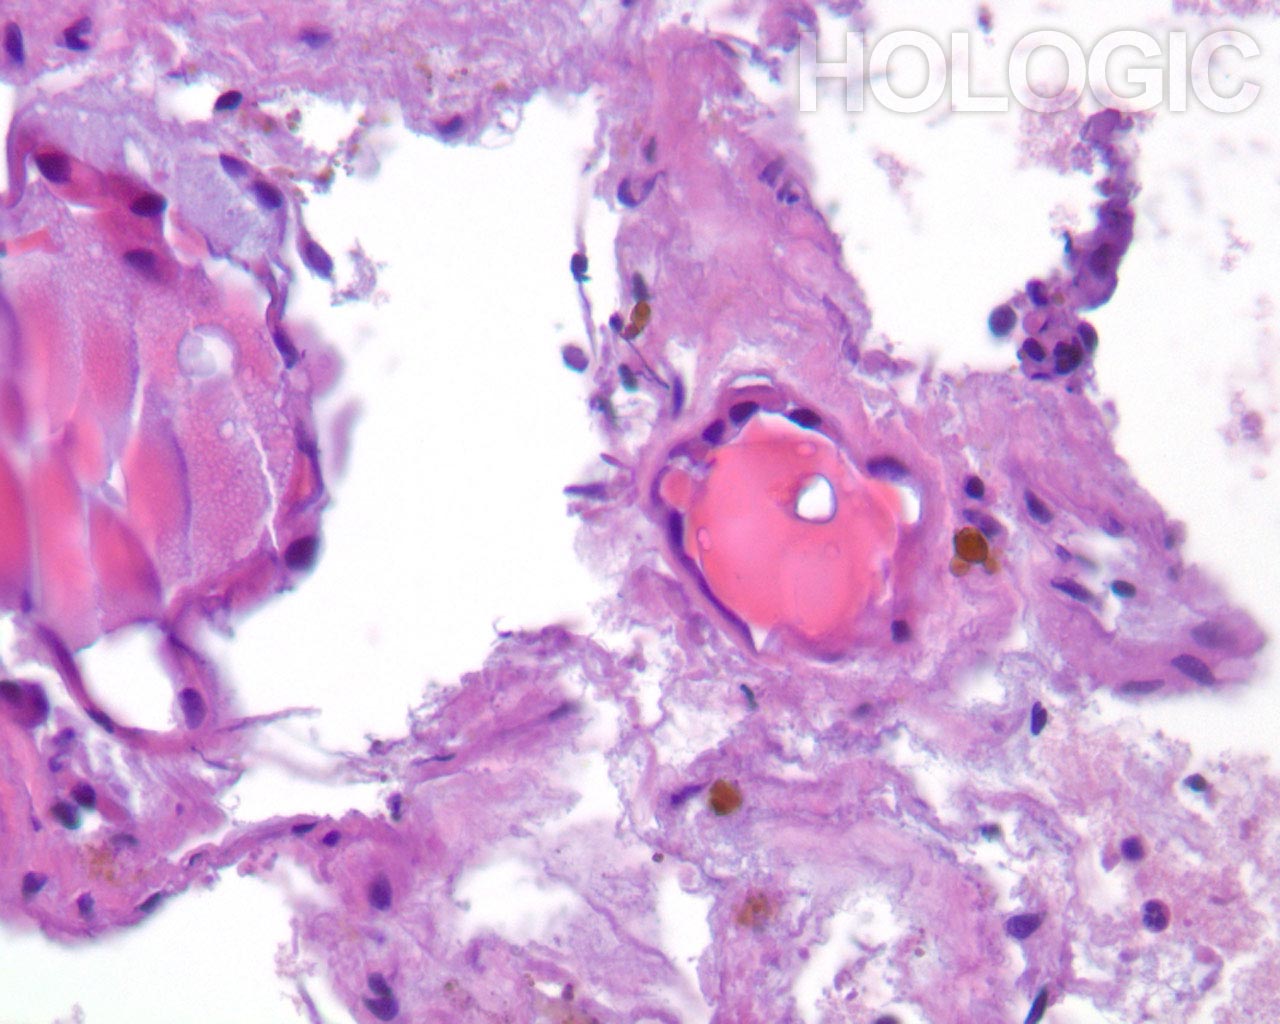

Papillair schildkliercarcinoom is een gemakkelijke diagnose als de nucleaire kenmerken goed ontwikkeld zijn en het monster goed is gepreserveerd. De beste diagnostische kenmerken van papillair schildkliercarcinoom zijn fijn verdeeld chromatine en een onregelmatige nucleaire envelop[2]. Het is interessant dat papillair schildkliercarcinoom het eerste voorbeeld is van een kanker waarbij de diagnostische nucleaire kenmerken rechtstreeks gerelateerd zijn aan de genen die de kanker veroorzaken (besproken in [10]). Een reeks van verschillende onregelmatigheden van de nucleaire envelop kan aanwezig zijn [11]. De chromatine van een papillair schildkliercarcinoom is verdeeld in erg fijne deeltjes en aangezien een groot deel van de chromatine gelijkmatig aan de nucleaire envelop kleeft, heeft zelfs een kleine vouw als gevolg dat de chromatine in de nucleaire envelop er uitziet als een lineair aggregaat of een langwerpige groef. Vooral intranucleaire cytoplasmische inclusies zijn kenmerkend voor een papillair schildkliercarcinoom, maar deze kunnen ook worden aangetroffen bij medullaire schildkliercarcinoom. Deze intranucleaire cytoplasmische inclusie ziet eruit als een scherpe demarcatie die afkomstig is van het heterochromatine in de nucleaire envelop, waardoor het een duidelijke donkerpaarse begrenzing van het cytoplasma vormt. Intranucleaire cytoplasmische inclusies komen zelden voor bij folliculaire neoplasmen [2].

Folliculaire neoplasmen tonen in tegenstelling tot een papillair schildkliercarcinoom compacte aggregaten van heterochromatine. Het is onze ervaring dat de kern van een papillair carcinoom grofweg kan worden onderscheiden van kernen van folliculaire carcinomen, doordat papillaire schildkliercarcinomen vaak meer lineaire aggregaten chromatine vertonen (erg oppervlakkige vouwen van de nucleaire envelop) dan ronde of geklonterde chromatinemassa’s. Deze kenmerken worden hieronder geïllustreerd.